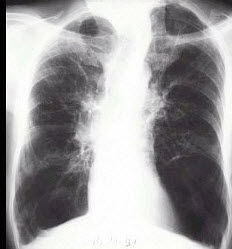

27、单项选择题 关于骨骼摄影条件的选择,错误的是()

134、单项选择题

男,65岁,呼吸困难伴胸闷1月余,胸片如图,最可能的诊断为()

A.气胸

B.肺结核

C.慢性支气管炎并肺气肿

D.肺部感染

E.支气管扩张